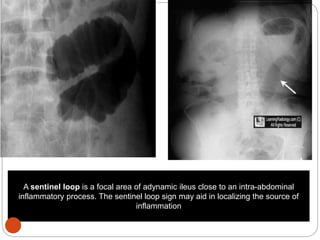

A sentinel loop is a focal area of adynamic ileus close to an intra-abdominal

inflammatory process. The sentinel loop sign may aid in localizing the source of

inflammation